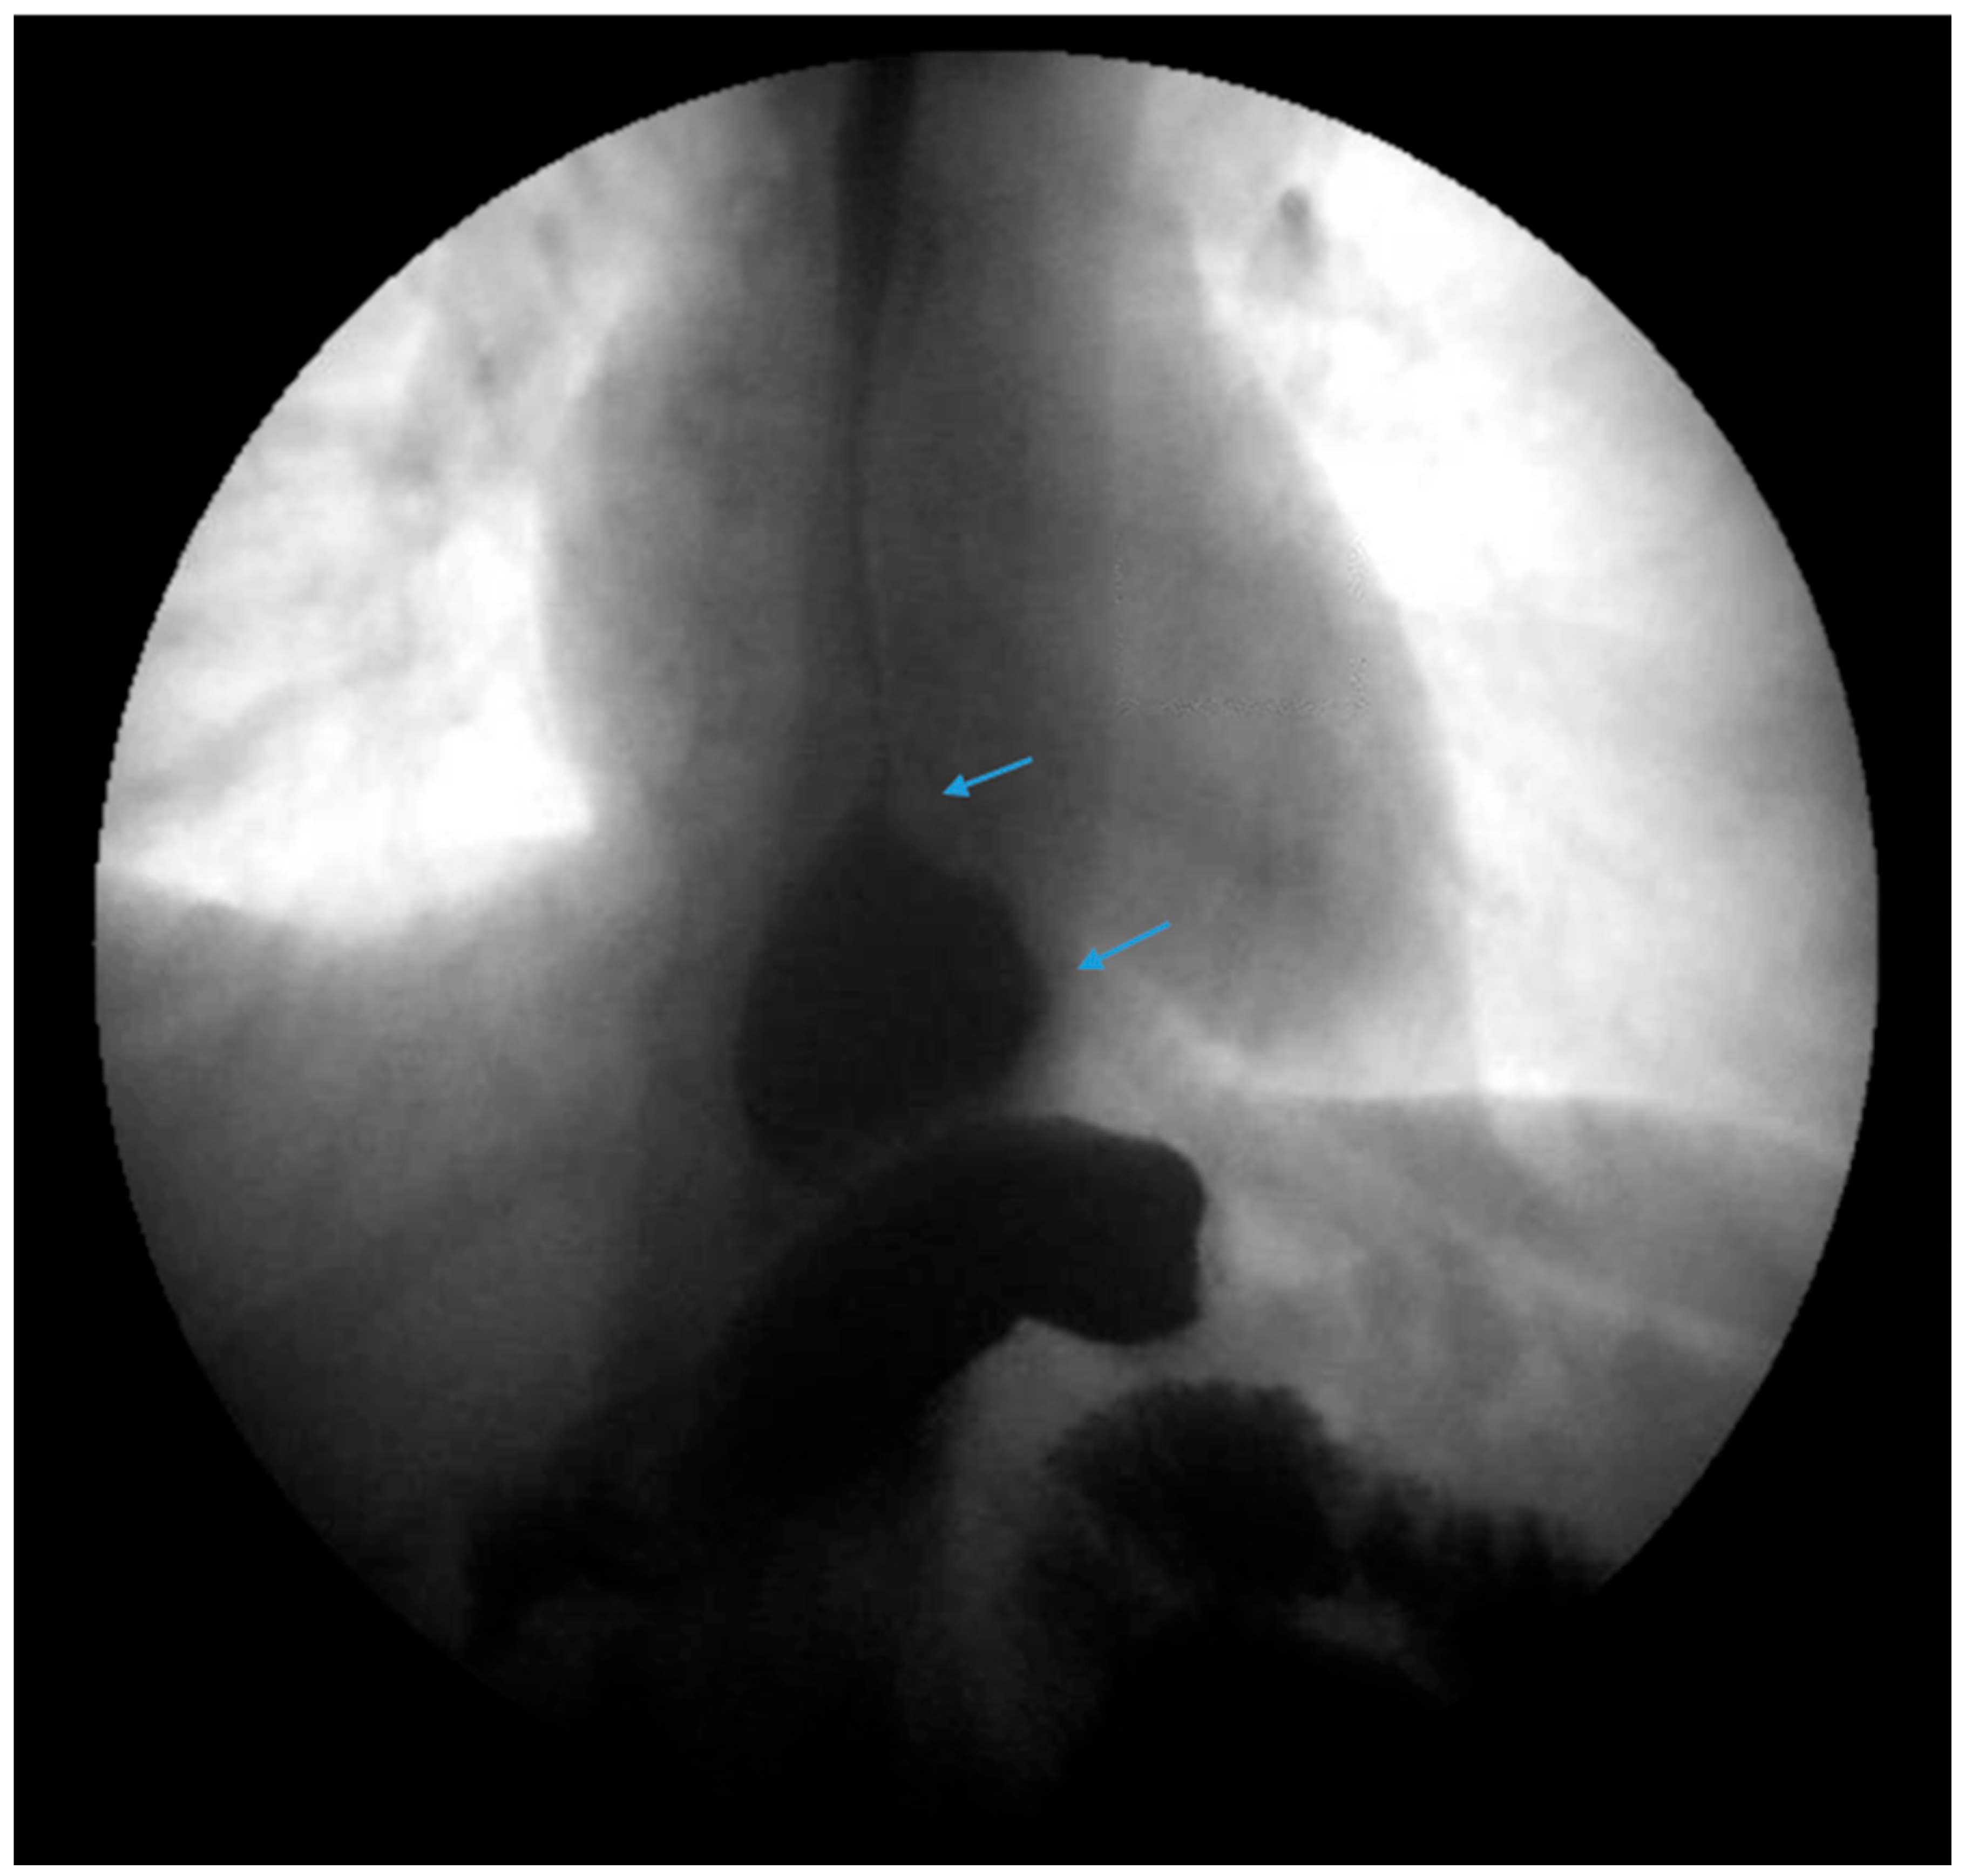

Figure 6.

Endoscopic images reveal a 3 cm hiatal hernia (arrows, top left) and Los Angeles Grade B esophagitis (arrows, top right) in the lower third of the esophagus with narrow-band imaging in a patient post-sleeve gastrectomy with symptoms of gastroesophageal reflux disease. The patient eventually required Roux-en-Y gastric bypass (arrow, bottom) and concomitant hiatal hernia repair, as demonstrated on upper gastrointestinal series.

Many studies reveal significant improvement in GERD symptoms and the use of acid suppression medications following conversion to RYGB. Studies by Langer et al. and Gautier et al. both reported that all patients were able to discontinue acid suppressive medications [73,74]. Parmar et al. revealed that 80% of patients discontinued acid suppressive medications whereas Hendricks et al. documented that 75% of patients had a complete resolution of GERD with conversion to RYGB [75,76]. A study by Strauss et al. concluded that 80.2% of patients who underwent conversion to RYGB had improvement in GERD symptoms [77].

The average rate of conversion from SG to RYGB due to GERD is approximately 5–10% [26,30,78]. In the SLEEVEPASS trial, the rate of conversion to RYGB was noted to be 6% [78]. In the SM-BOSS trial, the reported rate of conversion to RYGB was 9% [26]. In a meta-analysis of 46 studies by Yeung et al., 4% of patients underwent conversion to RYGB [30]. In a review of 73 cases, Langer et al. reported a conversion rate of 11% [73]. Some studies report a higher rate of conversion, although these studies had limitations [75,77,79].